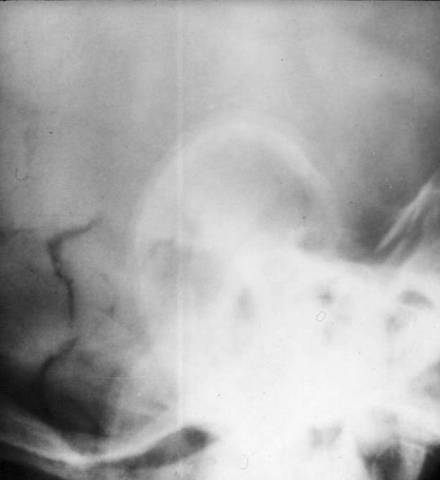

Calcified pinna-

Addison’s Disease